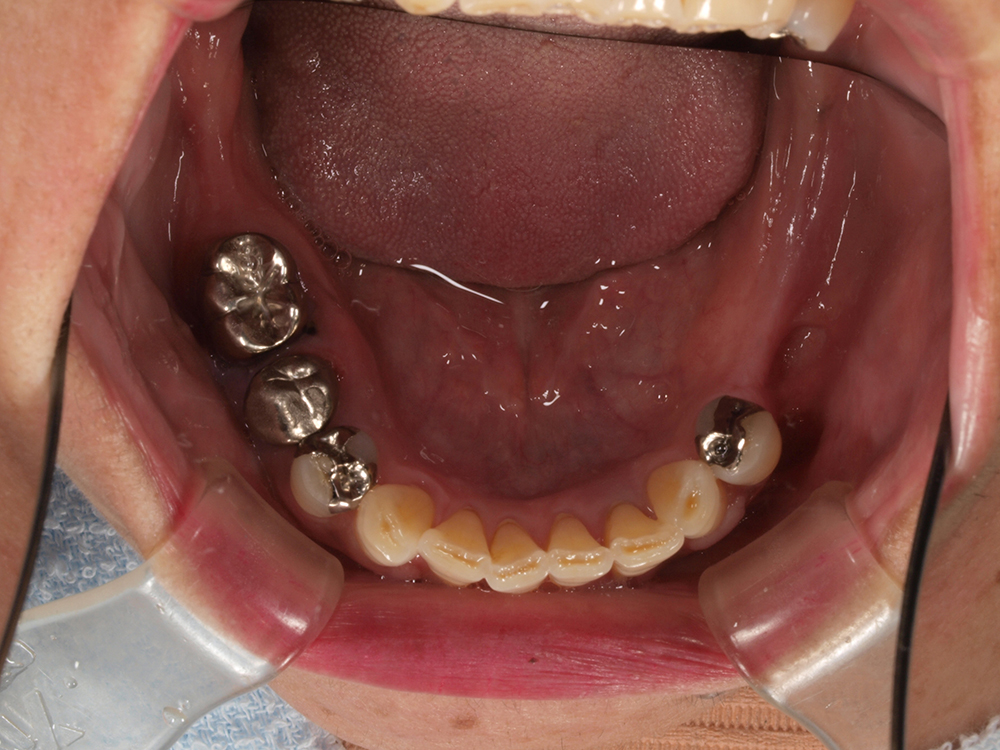

55歳 男性

- 主訴

- 前歯でしか咬めなく、食事を採るのに非常に困難で辛い

- 処置内容

- 上顎6本、下顎3本

- 治療費用

- 上顎:約230万(税込)下顎:約120万(税込)

- 治療期間

- 上顎:1年(仮歯まで8か月)下顎:8か月(仮歯まで5か月)

- リスク

- 上部構造物、仮歯の破折、術後の腫れ(3日)、人工歯根脱落リスクがあります